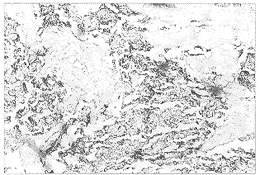

膀胱光鏡:依據WHO規定的肺小細胞癌的形態學診斷標準,膀胱小細胞癌腫瘤細胞光鏡下分為三類:燕麥細胞型、中間細胞型及混合細胞型。小細胞癌常呈不規則巢狀或瀰漫片狀排列,亦可見索狀排列,偶有癌細胞圍繞小血管排列成假菊形團結構。癌細胞體積較小,短梭形或淋巴細胞樣,細胞界限不清,細胞質稀少,核為圓形、橢圓形或梭形,核分裂多見,可見核重疊,染色質粗大,均勻分布,核仁不明顯。鏡下常見小細胞癌與移行細胞癌、腺癌或鱗癌等共存。

電鏡:電鏡下細胞排列緊密、胞漿稀少、細胞表面有細微突起,電鏡下主要特徵為胞漿內有為數不多的神經內分泌顆粒,直徑80~300nm。